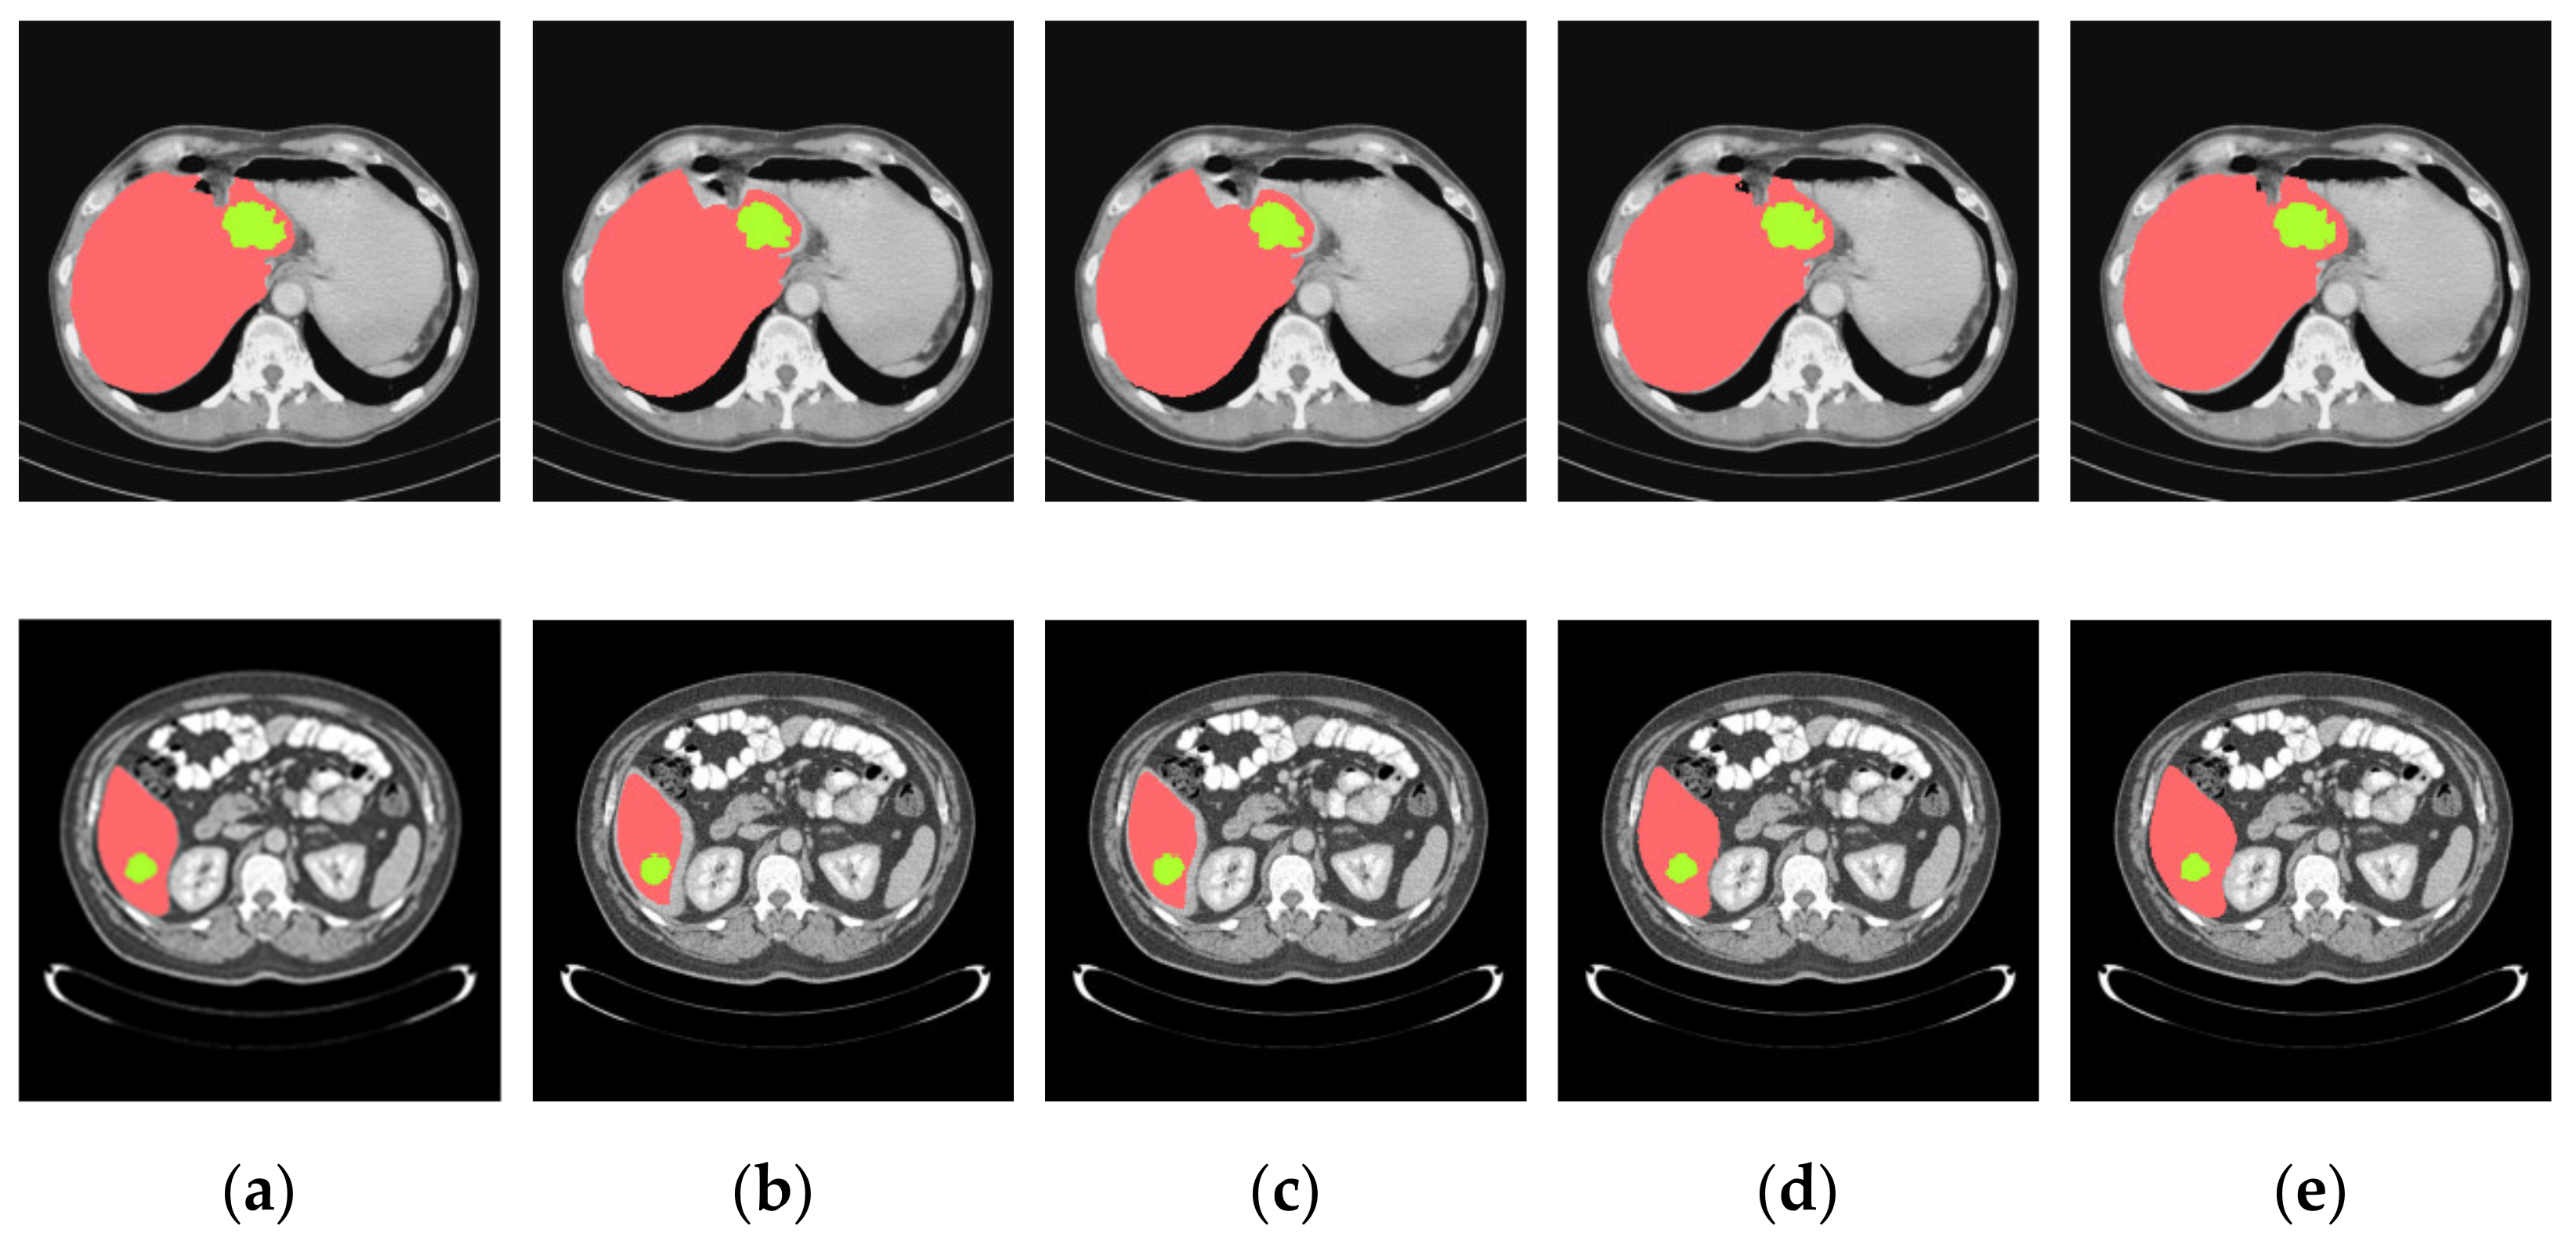

4.3.2. Analysis of Results in Three Patterns

4.3.3. Comparison of Various Algorithms